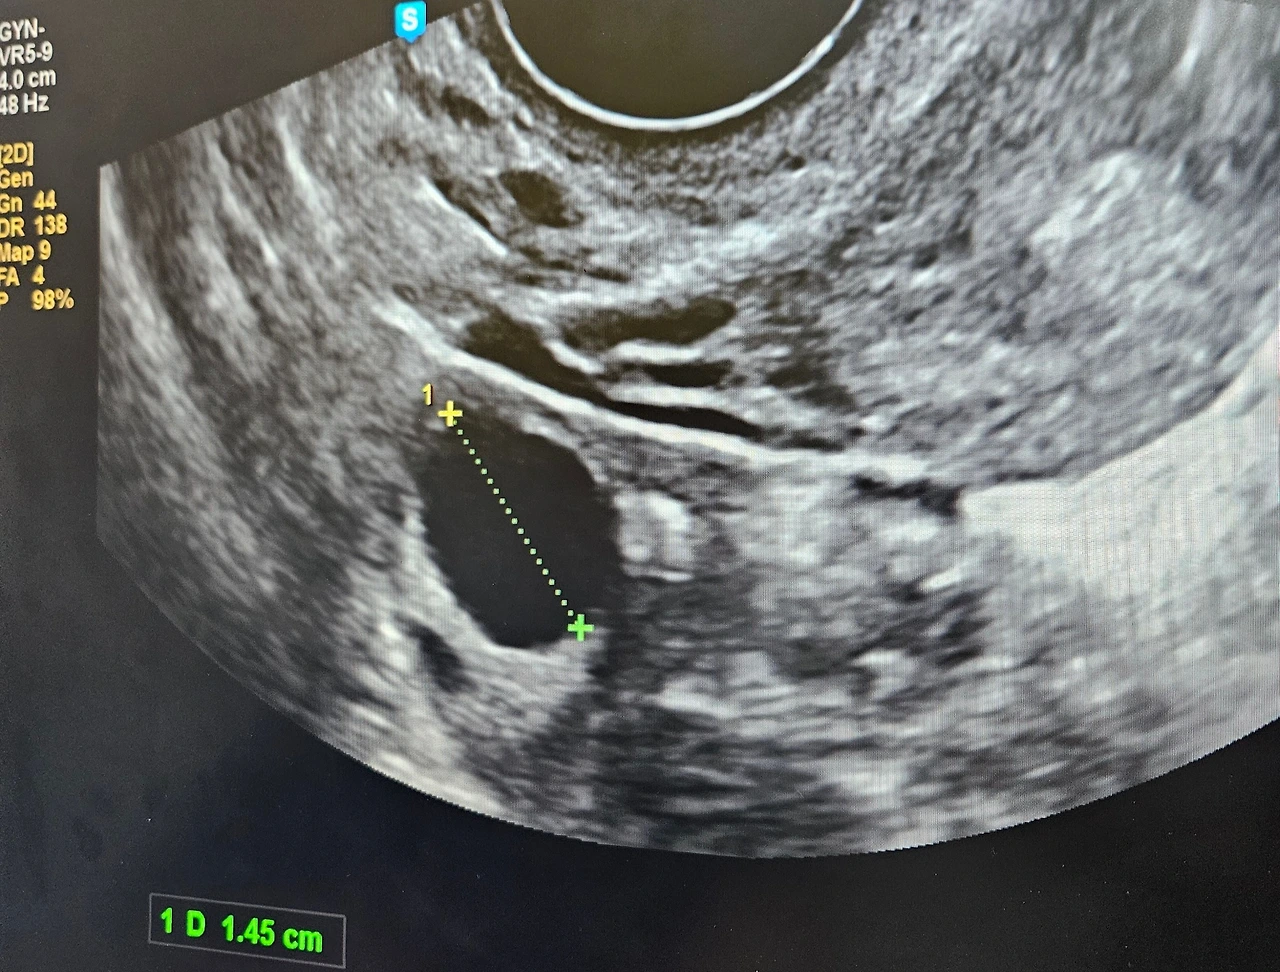

배란초음파로 본 난포크기는 1.6mm였고, 처음으로 의사에게 3일의 '숙제날'을 받았다.

(*난포는 하루에 0.2mm 정도 자라고, 2.0mm 이상으로 자라면 터져서 난자가 방출된다)

숙제 후에는 난포가 잘 터졌는지 확인해야 해서 26일, 다시 내원했다.

초음파를 보던 의사 선생님이 말하길,

"어? 난포가 안 터졌네?"

29일, 3차 배란초음파 보는 날.

"잘 터졌네요. 축하해요."

임신한 것도 아니고, 난포가 잘 터진 것도 축하할 일인 줄 이 날 알았다.